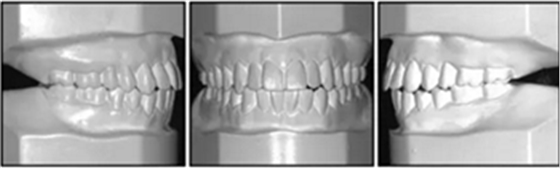

口內(nèi)相及模型:雙側(cè)磨牙、尖牙I類關(guān)系,良好的牙尖交錯關(guān)系,覆合、覆蓋正常。